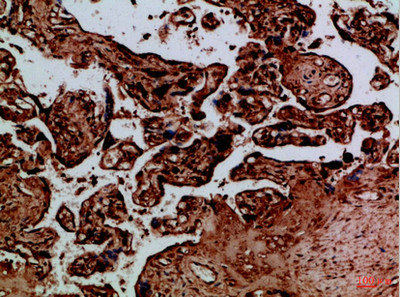

圖片:

應用范圍:IHC,ELISA

Application Recommended Dilution IHC IHC-p:1:50-300 ELISA 1:10000-20000 -